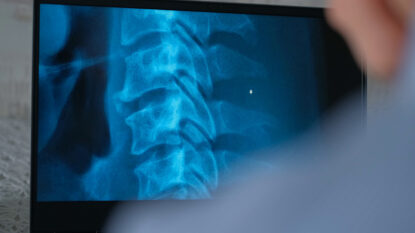

Artificial disc replacement involves diagnosing the cervical or lumbar spinal disc causing you challenges and replacing it with a prosthetic disc. The goal of this procedure is to relieve pressure on the surrounding nerves, relieve pain and restore your ability to move unimpeded.

In most cases, artificial disc replacement is preferable to a spinal fusion procedure. Both treatment options include removing the affected disc for pain relief. Lumbar disc replacement involves replacing a damaged disc with an advanced artificial disc. Spinal fusion involves fusing two or more vertebrae, often resulting in a long recovery and reduced mobility. Dr. Melikian will carefully assess your condition during your consultation and determine which procedure will best serve you.